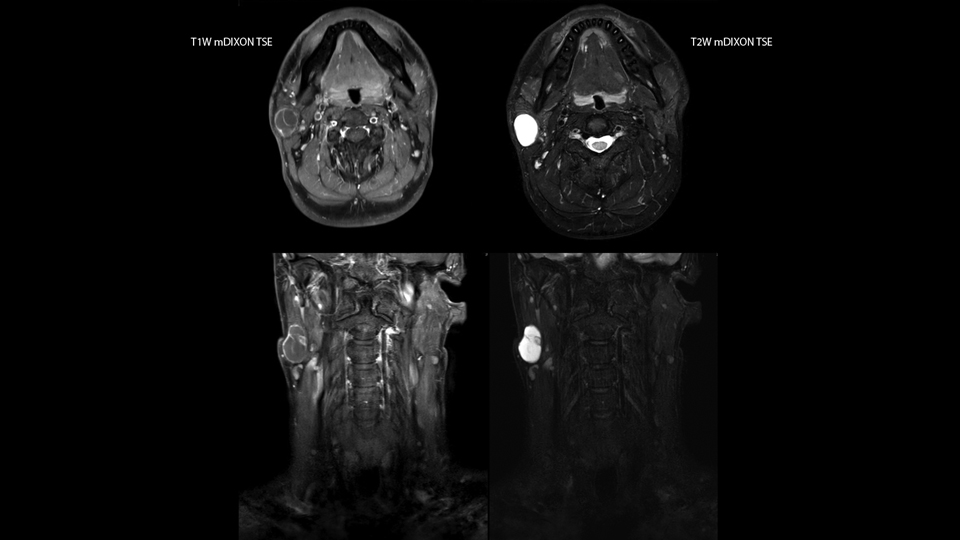

mDIXON TSE fat suppression helps DMG reduce repeats and supports diagnostic confidence

“Our DMG Lisle location includes a cancer center, so soft tissue neck scans, brachial plexus scans, and prostate scans are common. For these exams, mDIXON TSE provides excellent images with and without fat suppression all while helping us reduce repeats and work more efficiently,” Mr. Duffy says.

“With the 2-echo Philips mDIXON TSE the timing is short and the fatsat is very robust. The biggest thing is that you know your fat suppression will be good, even in thin patients or large patients that are off-center,” Mr. Sybesma says.

“Since we work in fixed time slots, not having to repeat scans is key for us,” Mr. Duffy adds. “With mDIXON TSE we get high quality results the first time – unless of course the patient absolutely jumps off the table. For us, that’s significant, because just a single repeat scan could put us behind schedule.

“mDIXON TSE raises our diagnostic confidence with its homogeneous

fat suppression. Neck exams and rheumatology patients are two examples where mDIXON TSE is especially useful,” Dr. Kaakaji says. “For us it’s also an efficiency boost in exams where we need pre and post T1-weighted images with great fat suppression.”